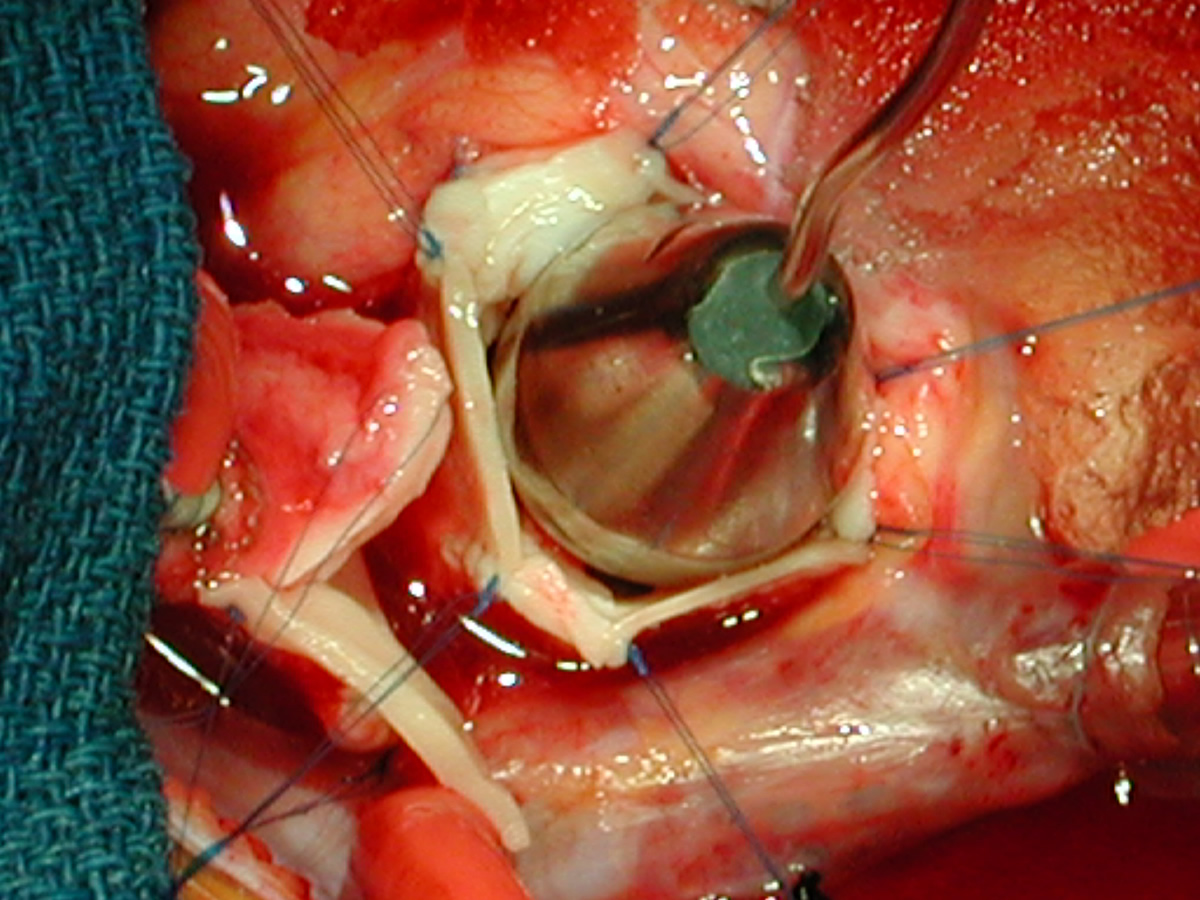

Aortic Stenosis Surgery in Infancy By JOHN F. KEANE, M.D., WILLIAM F. BERNHARD, M.D., AND ALEXANDER S. NADAS, M.D. SUMMARY During the past 14 years, 28 infants (23 males) underwent valvotomy for severe aortic stenosis at the ... Fetch Content